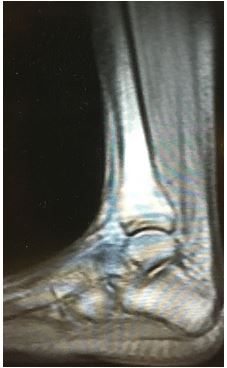

It was decided to get an urgent MRI, which confirmed inflammatory changes of the lower Achilles tendon (see image at right; click image once to enlarge). There was no cellulitis or joint effusion. Patient had recently taken a quinolone for a UTI.